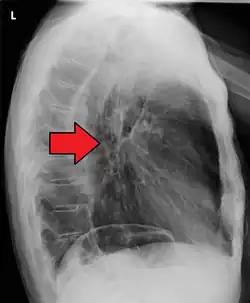

If the cancer has spread elsewhere, symptoms related to metastatic disease may appear. Common sites of spread include nearby lymph nodes, the liver, lungs and bone.[15] Liver metastasis can cause jaundice and abdominal swelling (ascites). Lung metastasis can cause, among other symptoms, impaired breathing due to excess fluid around the lungs (pleural effusion), and dyspnea (the feelings often associated with impaired breathing).